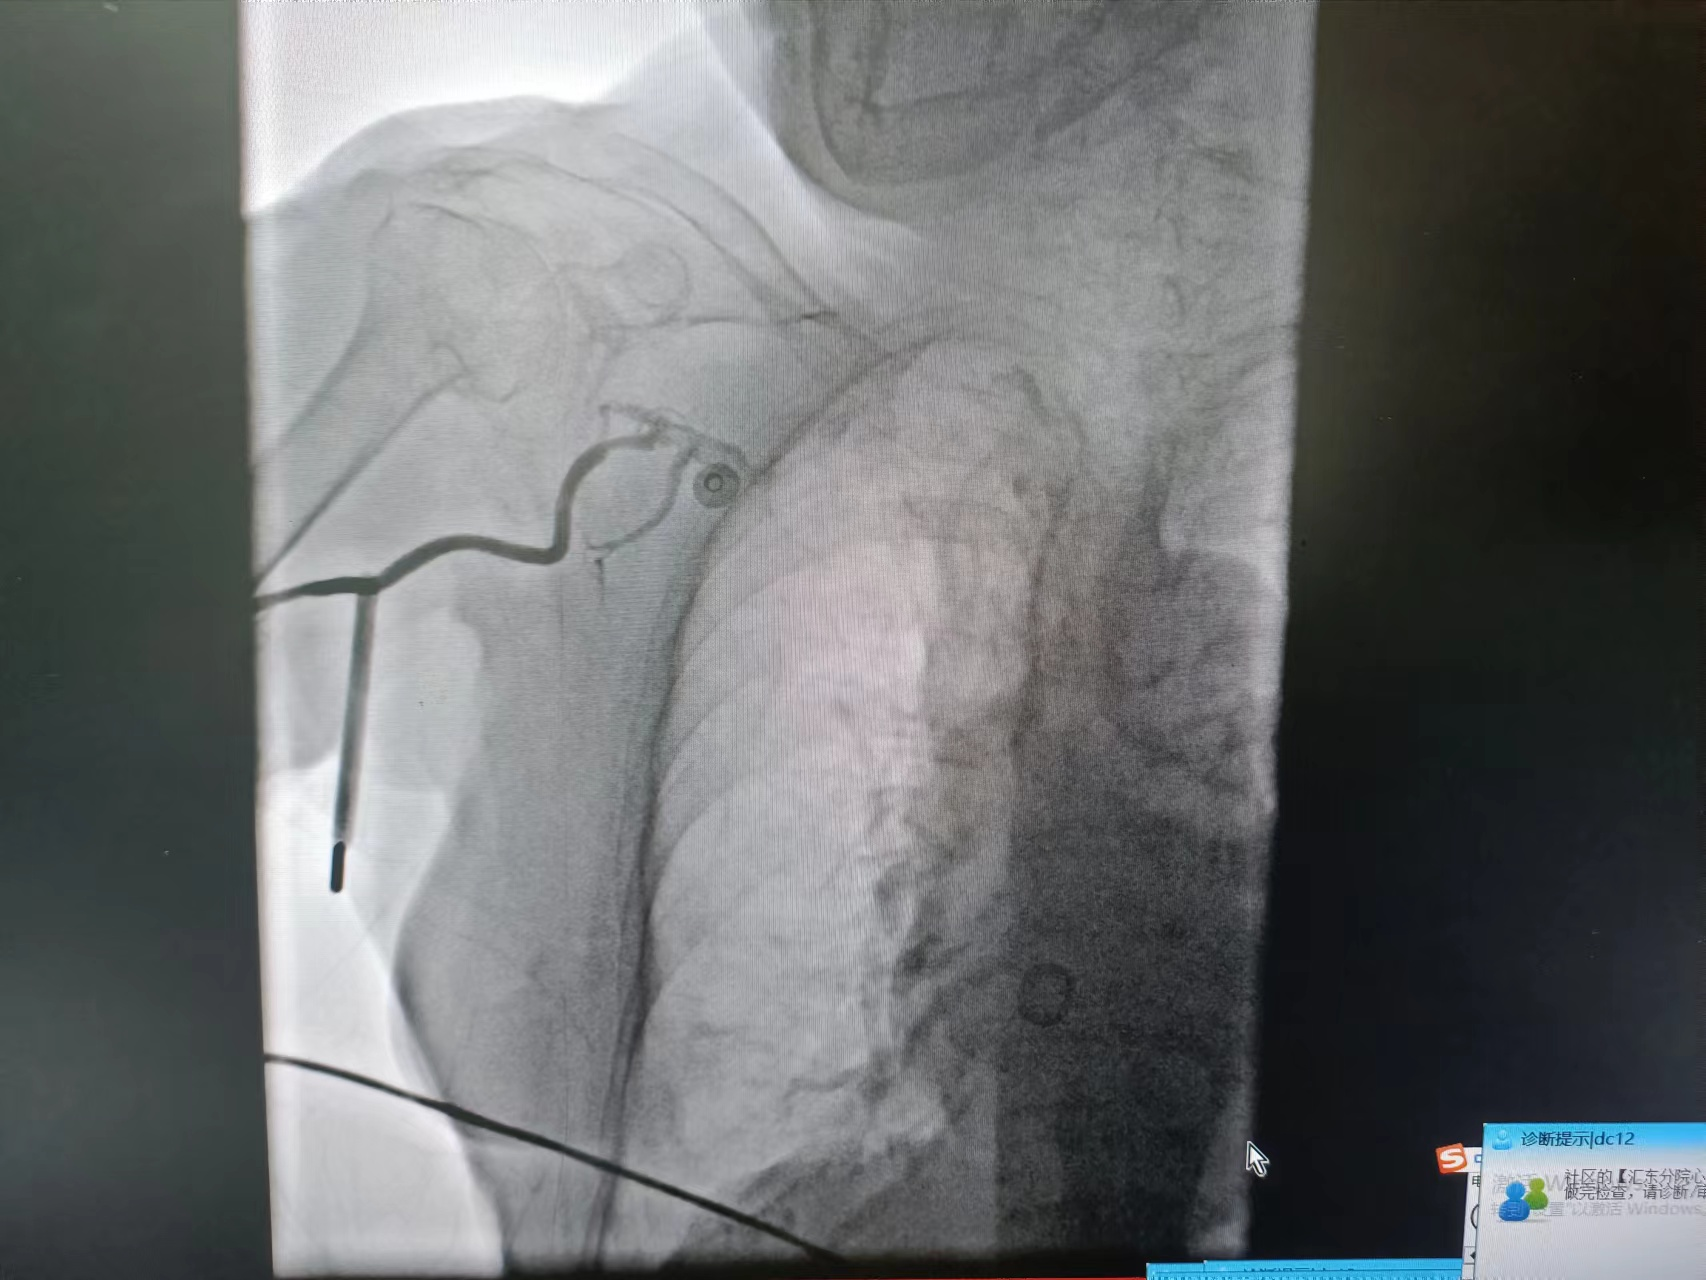

患者系102岁的超高龄女性,突发胸闷,伴大汗、乏力。外院就诊行心电图检查提示“心房颤动,II、III、AVF导联ST段显著抬高”,诊断急性下壁心肌梗死。由于患者体质差,年龄大等因素,当地医院转入我院,该患者合并房颤、血压低、精神差、症状重,生命危在旦夕,为救治患者,我院胸痛中心迅速启动导管室绿色通道,急诊行冠脉介入治疗。![]() 患者入介入室时已存在早期休克表现,脉搏微弱,桡动脉穿刺难度大,急诊备班的易主任凭借丰富的经验和高超的桡动脉穿刺技术,迅速为患者成功植入了桡动脉鞘管,并小心通过上肢扭曲的动脉顺利完成造影。经造影提示患者前降支开口闭塞,右冠脉开口闭塞,回旋支中段后闭塞,目前该患者仅有单支血管供血,心脏搏动微弱,随时可能发生死亡。易勇副主任争分夺秒,极短时间内顺利开通此次罪犯血管右冠脉,但植入支架后出现明显慢血流的情况,经给予硝普钠及反复冠脉抽吸处理后,患者血流恢复,成功完成手术。

![]() ![]() ![]() 术前冠脉造影